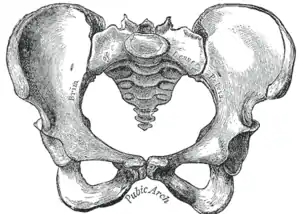

![]() Male pelvis |

![]() Female pelvis |

| Comparison between an android (left) and a gynecoid pelvis (right). | |

Traditional obstetrics have characterized four types of pelvises:

- Gynecoid: Ideal shape, with round to slightly oval (obstetrical inlet slightly less transverse) inlet.

- Android: triangular inlet, and prominent ischial spines, more angulated pubic arch.

- Anthropoid: the widest transverse diameter is less than the anteroposterior (obstetrical) diameter.

- Platypelloid: Flat inlet with shortened obstetrical diameter.